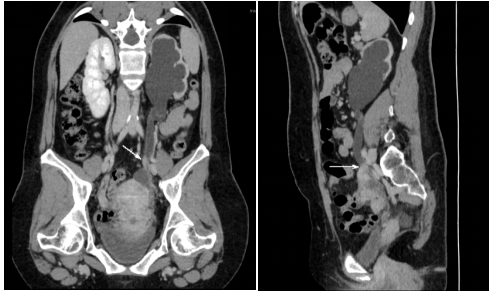

3.泌尿系增强CTU:左侧肾盂输尿管扩张积液,左侧输尿管盆段(S1水平)管腔狭窄,可见软组织密度结节影,平扫CT值约51HU,增强扫描CT值约95HU,边缘毛糙。

泌尿系增强CTU